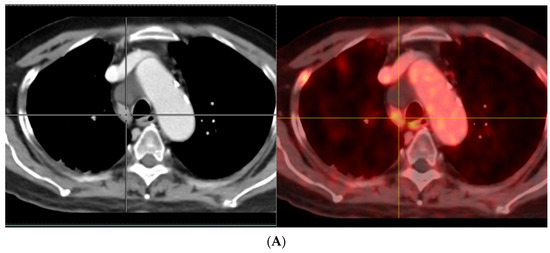

Following radical treatment for PCa with either external beam RT (EBRT) or radical prostatectomy (RP), between 27 and 53% of patients experience BCR [75]. There are differences in BCR definitions between and within the main curative contexts. According to the recent EAU guidelines on PCa, the threshold for best predicting further metastases after RP is PSA > 0.4 ng/mL and higher [76,77,78]. Prospective studies have reported the advantages of PSMA-targeted imaging in BCR in acquiring useful clinical information that could eventually change therapeutic strategies [69,79,80]. Various international guidelines recommend PSMA-PET imaging to be considered to clarify equivocal findings, especially if the results will directly and immediately influence therapeutic decisions (Figure 2).

Figure 2.

A 74-year-old man with adenocarcinoma of prostate gland (Gleason score 5 + 4 = 9) S/P radical prostatectomy with bilateral orchidectomy, developed rising serum PSA with level of 1.2 ng/mL which was suspected of BCR. His bone scan revealed equivocal lesions at left scapula, T8, and 12 vertebrae (A). He also performed 18F-PSMA PET/CT for evaluating BCR. There are multiple PSMA-avid lesions on MIP image (B) associated with multiple PSMA-avid mixed osteolytic and blastic metastases at multiple levels of vertebrae, both scapulae and multiple bilateral ribs as seen on coronal PET (C) and sagittal PET (D) images.